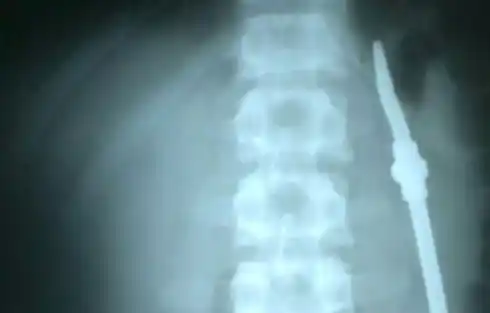

Un preso entrerriano se tragó una bombilla y debió ser hospitalizado

Un detenido de la Unidad Penal N° 1 de Paraná, partió una bombilla en dos y se la tragó. Testigos que estaban con él afirman que "no se explican el por qué de la situación". Fue intervenido quirúrgicamente.A raíz de la situación, el reo tuvo que ser trasladado rápidamente al hospital San Martín, en donde es intervenido quirúrgicamente."En un momento de disconformidad, este sujeto partió la bombilla y se la tragó. Testigos que estaban en el lugar no se explican por qué lo hizo. Fue trasladado rápidamente al hospital", manifestó el director de la cárcel, Rubén Gómez. (Fuente: ElOnce)